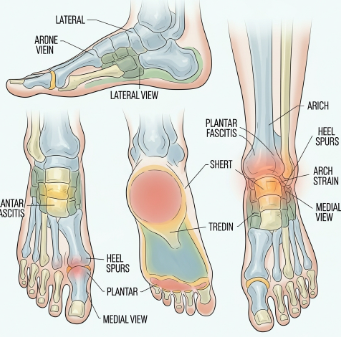

발뒤꿈치 통증은 발의 가장 아래쪽 뼈(종골)와 주변 조직에 발생하는 통증으로

1. 족저근막염(가장 흔한 원인)

발바닥의 두꺼운 섬유 조직(족저근막)에 미세 손상이 생겨 염증이 나타나는 질환입니다.

아침 첫 발 통증, 걷기 시작할 때 통증 증가, 오래 서 있으면 악화가 특징입니다.

2. 아킬레스건염

종아리 근육과 발뒤꿈치를 연결하는 아킬레스건에 염증이 생기는 경우입니다.

4. 종골(뒤꿈치 뼈) 뒤쪽 뼈돌기 – 해글룬드 병(Haglund deformity)

뒤꿈치 뼈 뒤쪽이 돌출되면서 신발 뒤축에 마찰이 생기고 통증이 발생합니다.

5. 신경 포착(티널 징후)

발바닥 신경이 눌리면서 저림·따끔함·찌릿한 신경통이 나타나는 경우도 있습니다.

- 엑스레이(X-ray)

- 뼈돌기, 골절 여부 확인

- 초음파 검사

- 족저근막 두께, 염증 정도 확인